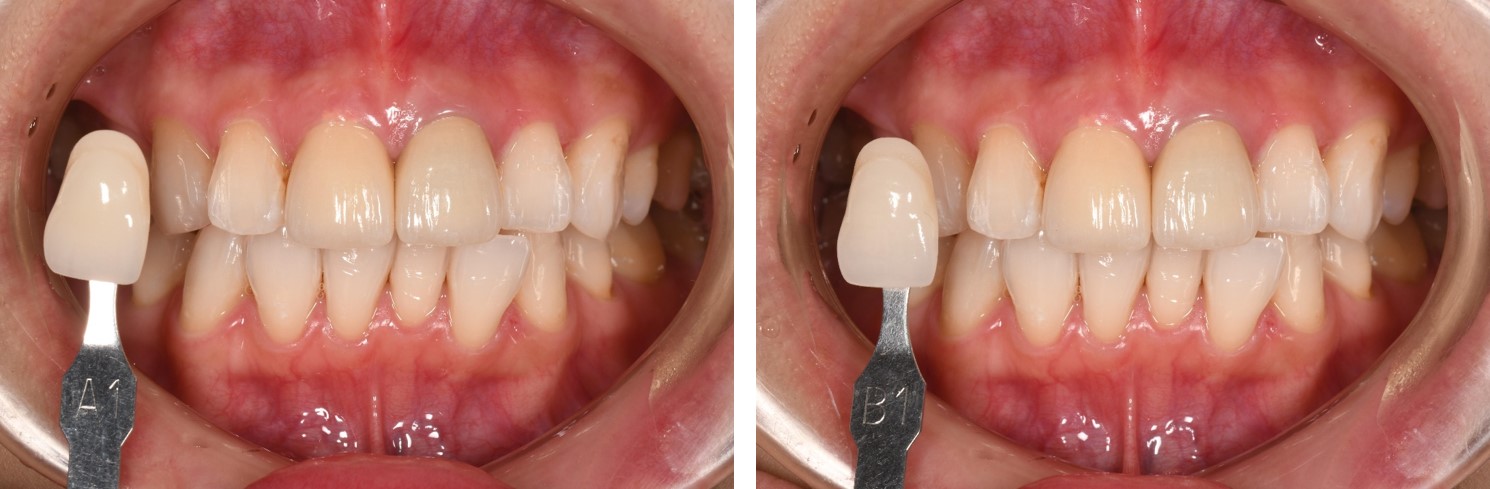

支柱牙與鄰牙照相比色